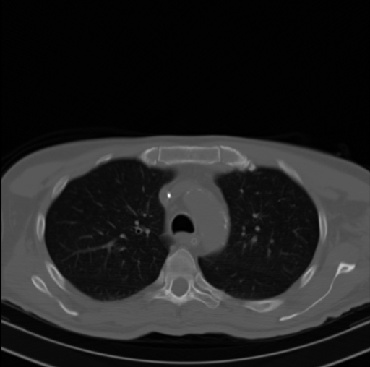

Early and reliable COVID-19 diagnosis based on chest 3-D CT scans can assist medical specialists in vital circumstances. Deep learning methodologies constitute a main approach for chest CT scan analysis and disease prediction. However, large annotated databases are necessary for developing deep learning models that are able to provide COVID-19 diagnosis across various medical environments in different countries. Due to privacy issues, publicly available COVID-19 CT datasets are highly difficult to obtain, which hinders the research and development of AI-enabled diagnosis methods of COVID-19 based on CT scans. In this paper we present the COV19-CT-DB database which is annotated for COVID-19, consisting of about 5,000 3-D CT scans, We have split the database in training, validation and test datasets. The former two datasets can be used for training and validation of machine learning models, while the latter will be used for evaluation of the developed models. We also present a deep learning approach, based on a CNN-RNN network and report its performance on the COVID19-CT-DB database.